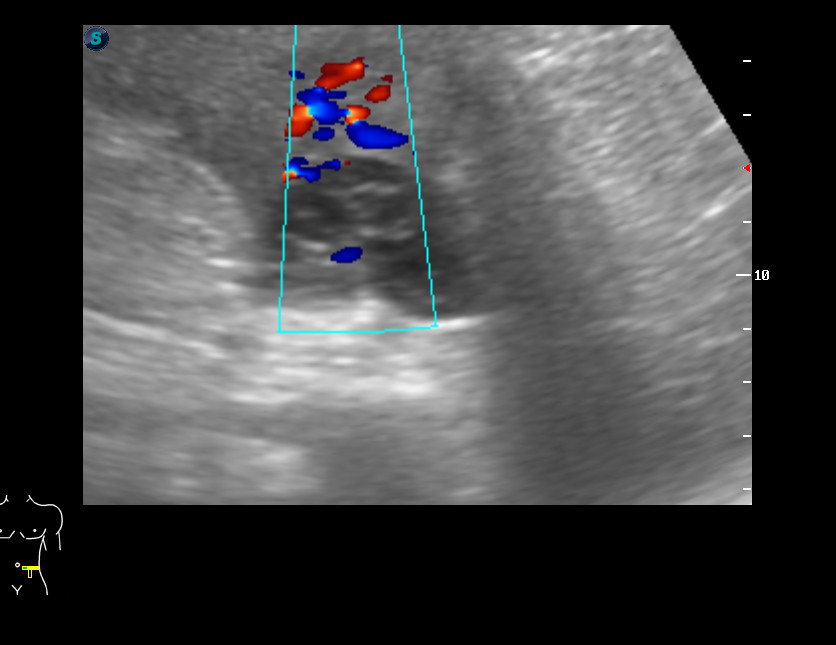

Мужчина 50 лет, жалоб не предъявляет.

В нижнем полюсе левой почки обнаружена киста с солидным внутренним компонентом. Предположена опухоль в кисте.

КТ - киста Bosniak III.

Выполнена резекция опухоли.

Гистологически - светлоклеточная карцинома.